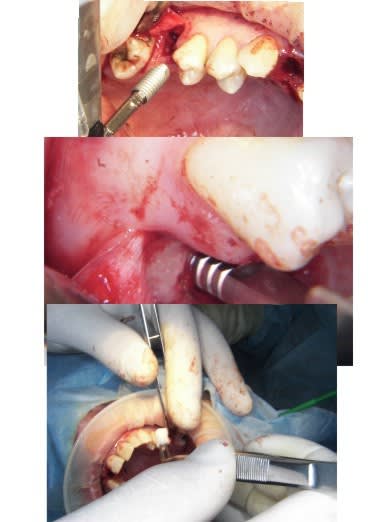

j'ai fait une bonne matinée implanto ce matin avec mélange des techniques 2 Summers avec un mélange expanseurs/condenseurs Meissinger, ostéotomes impactés pour la corticale qui faisait de la résistance, eponge pour la membrane, puis une reprise d'echec sur une mise en vitrine immédiate (fracture en mangeant une frite calcinée, à un mois!le 14/07)déposé le 15/07 mais avec mouvements pendant 24 heure et de 3.4mm j'ai du passer à 5.2!

les photos d'hier avec la mise en vitrine immediate et la reprise

--

xbk